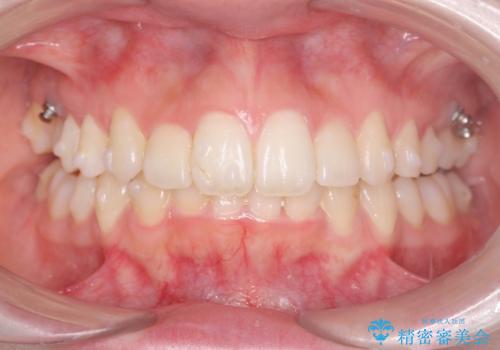

サクソフォン(アルト)の演奏で崩れてしまった歯並び、マウスピース矯正治療

口腔内の清掃状態の良さに加えて、マウスピースを毎日きっちりと装着し、しっかりと使用していただけたことからワイヤー矯正は行わずにきれいに歯並びを治すことができました。

途中顎位が変わり、マイクロインプラントを併用した上顎臼歯の遠心移動が必要となったため治療が長期化しました。